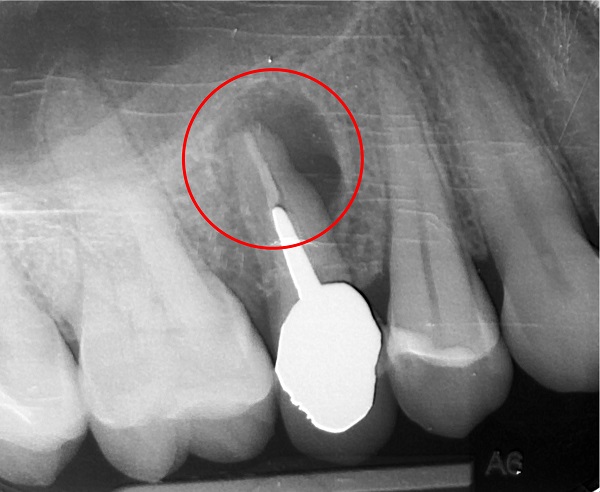

Infatti è una reazione infiammatoria di tipo cronico (cioè che dura da molto tempo) costituita da un ammasso di cellule addette alla difesa dell’organismo che si dispongono a cerchio attorno all’apice del dente, quasi a costituire un tappo, un argine alla grande quantità di batteri che proviene dal canale del dente non ben devitalizzato oppure dal “nervo” morto e non asportato (polpa dentale necrotica).

Ora che sappiamo cos’è il granuloma (si badi bene una radiografia può far sospettare la sua esistenza!) e da cosa è causato, è facile capire come si “combatte”. E’ sufficiente che il dentista faccia una corretta terapia canalare (la cosiddetta devitalizzazione) per risolvere definitivamente il problema. Infatti se il canale dentale verrà perfettamente deterso, preparato ed otturato in tutta la sua lunghezza fino all’apice, il granuloma si riassorbirà progressivamente perché finirà il suo compito di difesa. Succede, invece che alcuni dentisti intervengono chirurgicamente per eliminare il granuloma, soprattutto sugli incisivi dove è particolarmente semplice una devitalizzazione (terapia canalare). Intervengono asportando il granuloma e parte della punta del dente (apicectomia). Solo alcuni otturano anche il canale dall’alto, operazione questa (retrograda), che permetterebbe, in discreta misura, di evitare una ricaduta (recidiva del granuloma). recidiva, che altrimenti è inevitabile.